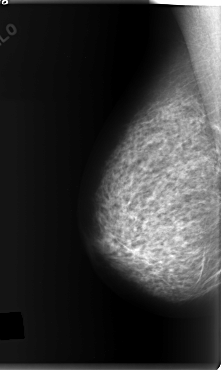

C_0148_1.LEFT_CC

LEFT_CC LINES 6008 PIXELS_PER_LINE 3592 BITS_PER_PIXEL 12 RESOLUTION 50 OVERLAY

FILE: C_0148_1.LEFT_CC.OVERLAY

TOTAL_ABNORMALITIES 1

ABNORMALITY 1

LESION_TYPE MASS SHAPE ARCHITECTURAL_DISTORTION MARGINS ILL_DEFINED

ASSESSMENT 4

SUBTLETY 2

PATHOLOGY MALIGNANT

TOTAL_OUTLINES 1

BOUNDARY